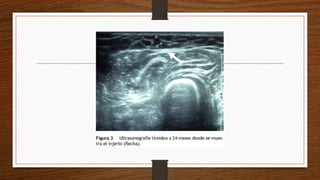

• Además en esta área es fácil realizar ultrasonografías y gammagrafías de

control con una fácil identificación del tejido.

• 3) presencia del injerto y su vascularidad mediante una ultrasonografía